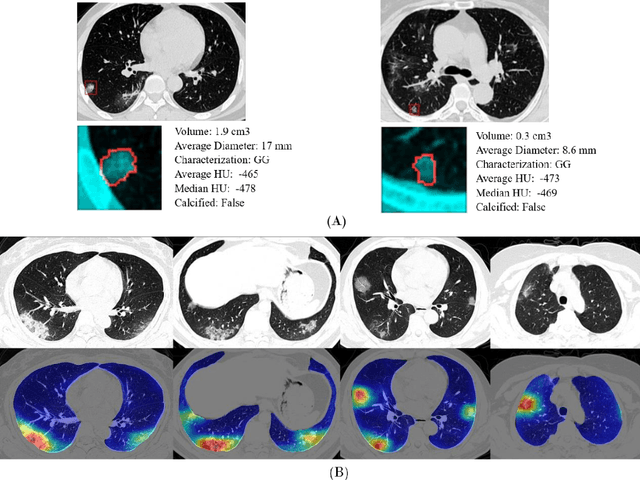

Abstract:Purpose: Develop AI-based automated CT image analysis tools for detection, quantification, and tracking of Coronavirus; demonstrate they can differentiate coronavirus patients from non-patients. Materials and Methods: Multiple international datasets, including from Chinese disease-infected areas were included. We present a system that utilizes robust 2D and 3D deep learning models, modifying and adapting existing AI models and combining them with clinical understanding. We conducted multiple retrospective experiments to analyze the performance of the system in the detection of suspected COVID-19 thoracic CT features and to evaluate evolution of the disease in each patient over time using a 3D volume review, generating a Corona score. The study includes a testing set of 157 international patients (China and U.S). Results: Classification results for Coronavirus vs Non-coronavirus cases per thoracic CT studies were 0.996 AUC (95%CI: 0.989-1.00) ; on datasets of Chinese control and infected patients. Possible working point: 98.2% sensitivity, 92.2% specificity. For time analysis of Coronavirus patients, the system output enables quantitative measurements for smaller opacities (volume, diameter) and visualization of the larger opacities in a slice-based heat map or a 3D volume display. Our suggested Corona score measures the progression of disease over time. Conclusion: This initial study, which is currently being expanded to a larger population, demonstrated that rapidly developed AI-based image analysis can achieve high accuracy in detection of Coronavirus as well as quantification and tracking of disease burden.